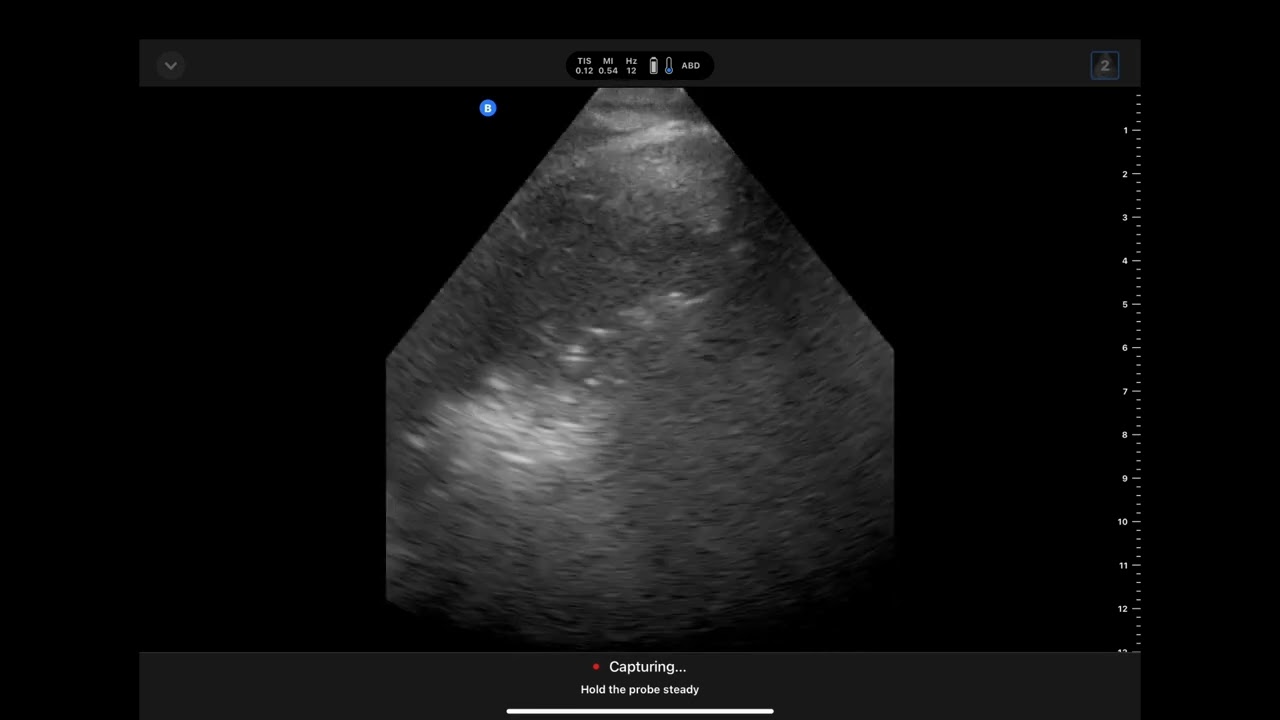

Overview of Butterfly IQ3 ultrasound probe

In the first of a series on handheld ultrasounds, Dr. Guttman provides an overview of the Butterfly IQ3, including the latest features.

Considering purchasing a handheld #POCUS machine? Checkout this video on the Butterfly IQ3 to see if it's right for you.